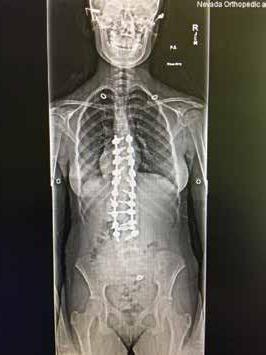

Total disc replacement (TDR) may be an alternative to spinal fusion for patients with cervical or lumbar herniated discs or degenerative disc disease.

The goals of total disc replacement surgery are to maintain segmental spinal motion, relieve pain, increase activity, restore disc height and proper spine curvature, and reduce post-operative recuperation time.

If you are experiencing neck or back pain and are considering surgery, isn't it worth your time to schedule an appointment with Dr. Jason E. Garber to nd out if motion preservation technology is an option for you?

Dr. Garber is one of Southern Nevada's most experienced spinal surgeons and a leader in arti cial disc replacement surgery.